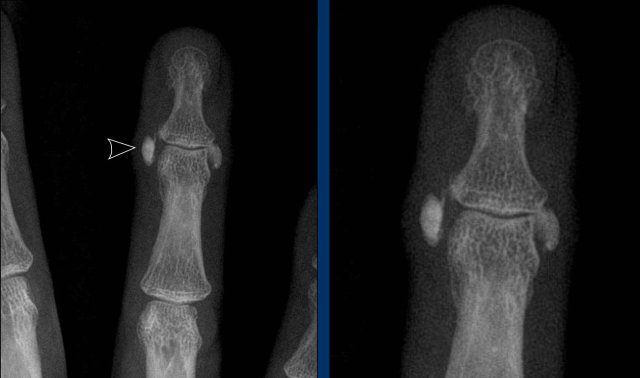

Progressive psoriatic arthritis

1. The picture on the left shows marginal erosions (black arrow) and subtle bone formation (blue arrow) of the IP joint.

2. Later on, it progresses to the typical pencil-in-cup deformation.

The distribution and the bone formation makes the diagnosis of rheumatoid arthritis unlikely.

The marginal erosions and the absence of DIP involvement in other joints makes the diagnosis of erosive osteoarthritis unlikely, although pencil-in-cup can look like the gullwing deformity in erosive osteoarthritis.